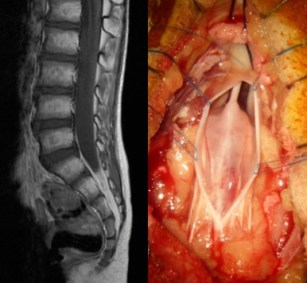

le bilan initial a pour but de réaliser un grading tumoral : recherche de métastases au niveau crânien ou spinal, recherche de cellules tumorales dans le LCS

on recherche systématiquement des métastase par l‘IRM cranio-spinale.

la chirurgie a pour but premier le diagnostic histopathologique, qui peut être obtenu par abord direct de la tumeur, ou par abord d’une métastase, si la lésion à biopsier est de volume suffisant pour obtenir le diagnostic histopathologique et le grading de biologie moléculaire.

lorsque la masse tumorale métastatique est volumineuse, une chirurgie de debulking peut être nécessaire afin de préparer le patient pour la radio-chimiothérapie.